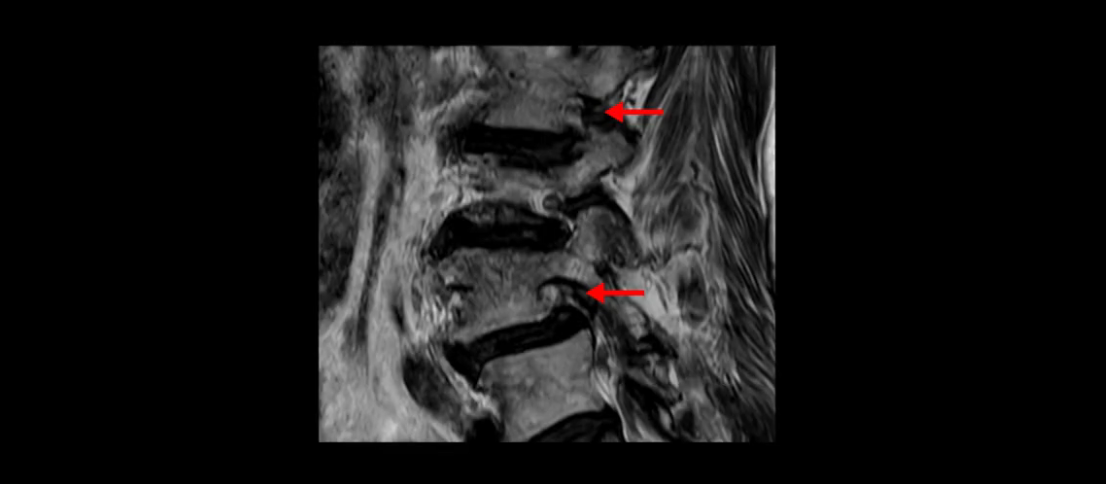

이분 MRI 보시면 허리 3마디의 퇴행이 매우 심합니다.

4번 5번에는 뼈가 밀려 나간 전방전위증도 있고,

또 척추관협착도 매우 심합니다.

척추관이 심하게 좁아져 있습니다.

이렇게 여러 마디가 안 좋고 뼈도 밀려 나가 있으니까 나사박는 수술해야 하는데, 대학병원에서도 수술을 한 번에 못 하고 두 번에 나눠서 해야 한다고 들으셨습니다. 왼쪽으로 신경가지가 빠져나가는 추간공도 많이 좁아져 있습니다.

이렇게 신경 구멍들이 좁아져 있고 신경이 눌리니까 엉덩이와 다리가 너무 저리고 아파서 아예 일어서질 못하니까 휠체어를 타고 병원에 내원하셨는데요. 그럼 어떻게 이분처럼 신경이 눌려있는 환자분들을 수술 없이 치료해서 잘 걷게 만들고 엉덩이와 다리가 저리고 아픈 증상이 사라지게 할까요? 지금부터 설명해 드립니다.